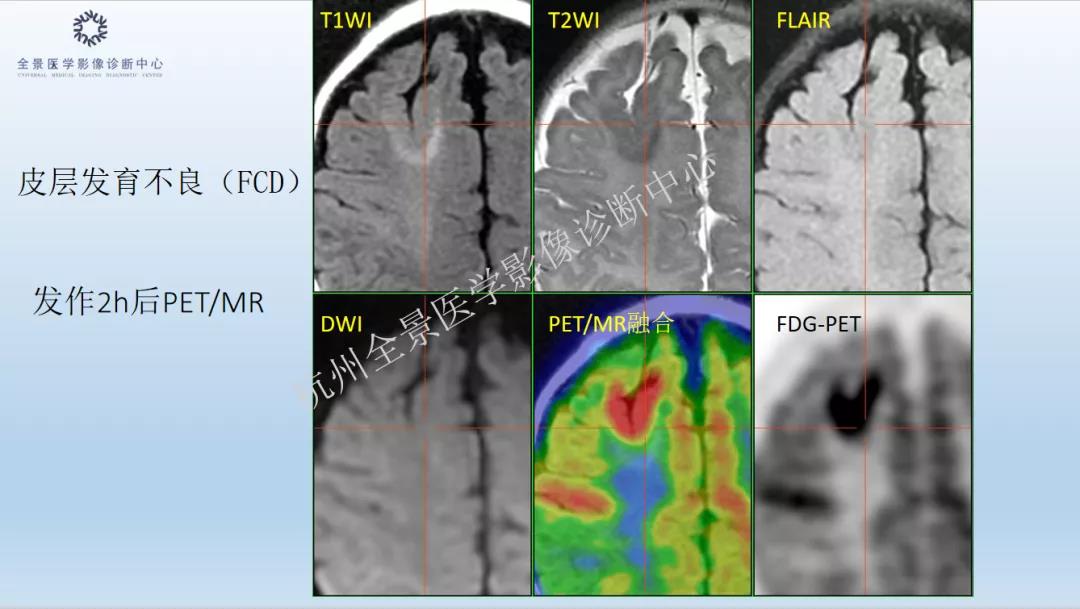

1. 《PET/MR多模态显像在神经系统中的应用》 汇报人:许远帆

案例展示: